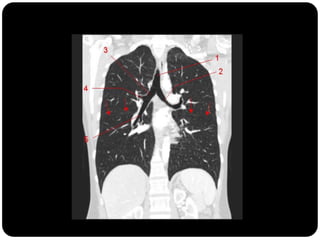

Brônquios segmentares

Esquerdo



Pulmão direito

Superior: direito

inferior: esquerdo

 Pulmão direito:

 LSD: anterior, apical e posterior;

 LM: medial e lateral;

 LID: superior, basal medial, basal lateral,

basal anterior, basal posterior;

 Pulmão esquerdo:

 LSE: apicoposterior, anterior,

superior(língula), inferior(língula);

 LIE: segmento superior, basal antero-

medial, basal lateral e basal posterior;